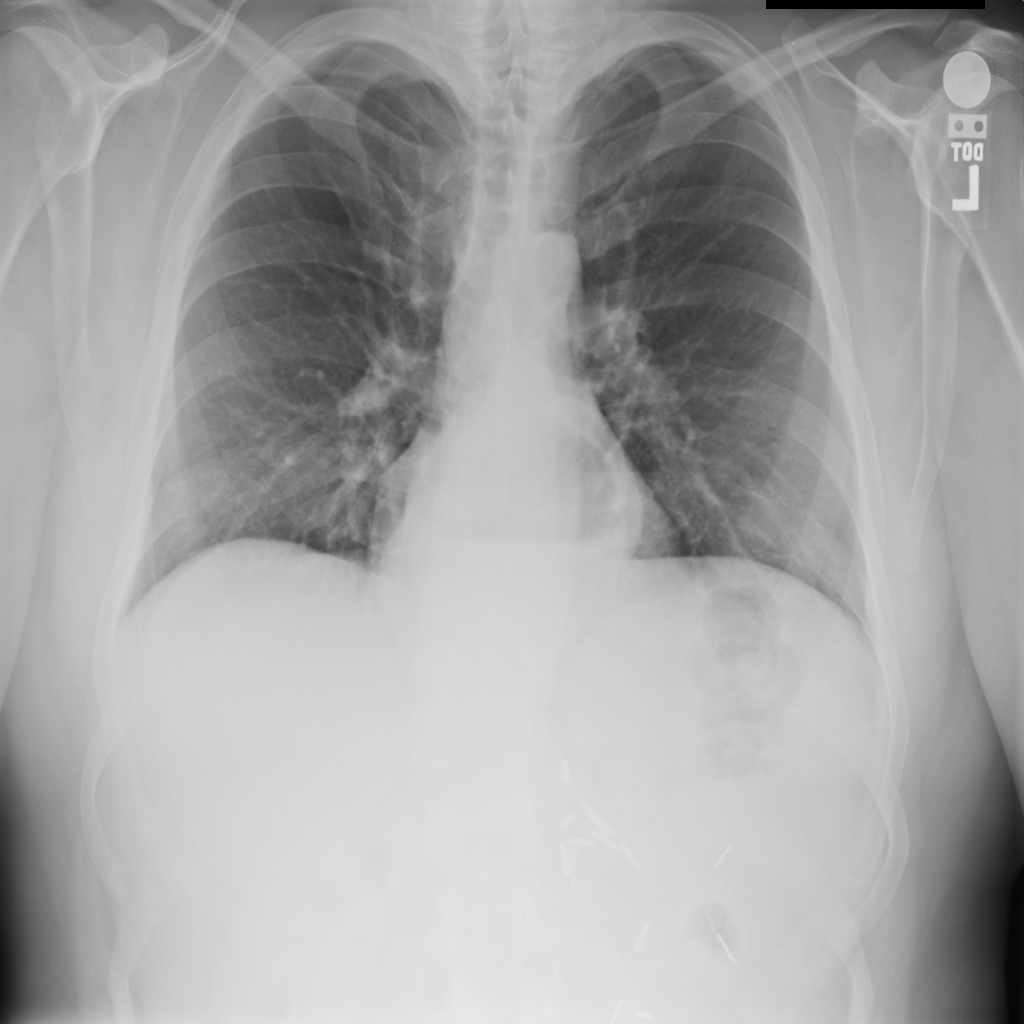

Showing up to 90 reference images for Hernia.

PAT-0ABD · IMG-000Hernia

PAT-0ABD · IMG-000

PA